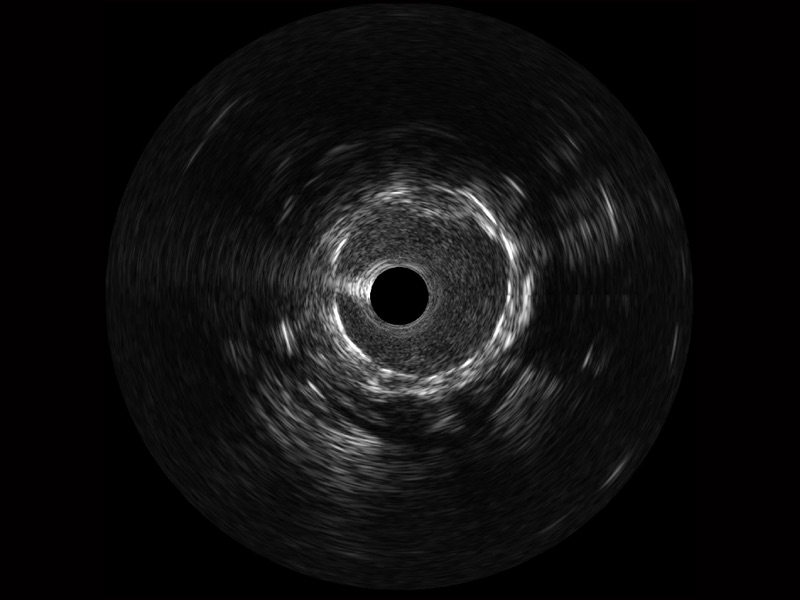

• 16877太阳集团宽频IVUS图像

• 传统IVUS图像

对比传统IVUS导管成像,16877太阳集团宽频IVUS图像的近场支架梁显影更细腻,远场中膜外血管仍清晰可辨,兼顾远中近,兼顾分辨力与穿透深度